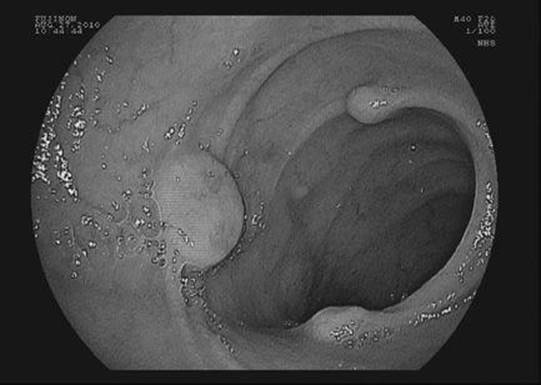

True/False: Small bowel carcinoid tumors are almost always solitary.

Figure 23-2 See also color plate.

False. Multicentric carcinoid tumors, as shown in the Figure 23-2, are seen in up to 33%.